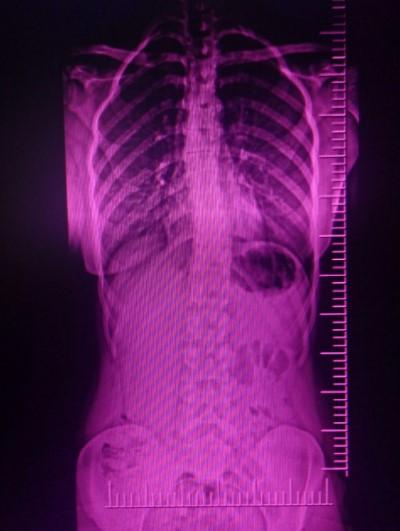

Skolyoz, insan omurgasının sağa ve sola doğru eğrilmesidir.

Sağlıklı bir insanın omurgasına yandan bakıldığında omurganın düz olmadığı görülür. Fakat arkadan bakıldığında ise dümdüz bir omurga ile karşılaşılır. Eğer omurganın arkadan duruşunda sağa sola ve rotasyonel deformite varsa buna skolyoz yani omurga eğriliği denir.

Skolyoz (Omurga eğriliği) bir hastalık değildir, bulgudur. Birçok hastalığa bağlı olarak çıkabilmektedir. Skolyozun çeşitli nedenleri olabilir. Bugün en sık görülen skolyozun, nedeni ise hala bilinmemektedir.